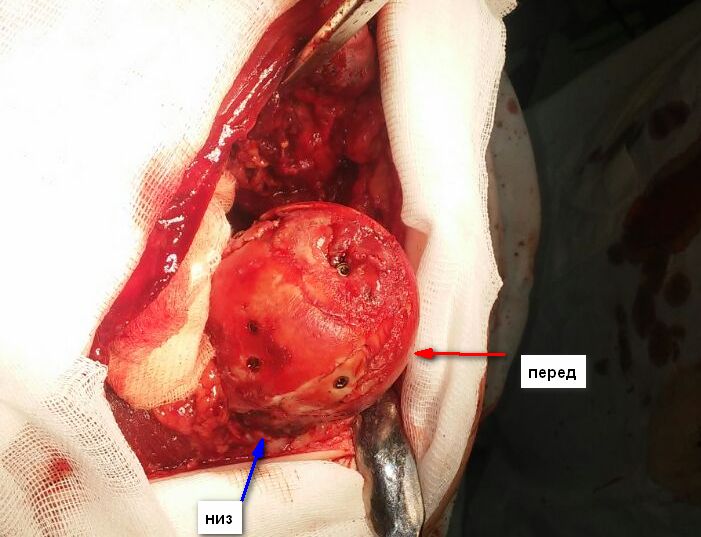

[Ortho] Pipkin II

Стоило ли заниматься остеосинтезом в этом случае?

Мужчина, 50 лет, активный, падение с высоты. При поступлении вправление

вывиха, других повреждений нет Без значимой сопутствующей патологии, не

курит. Стоило ли выполнять остеосинтез при таком оскольчатом переломе

или сразу пойти на ТНА?